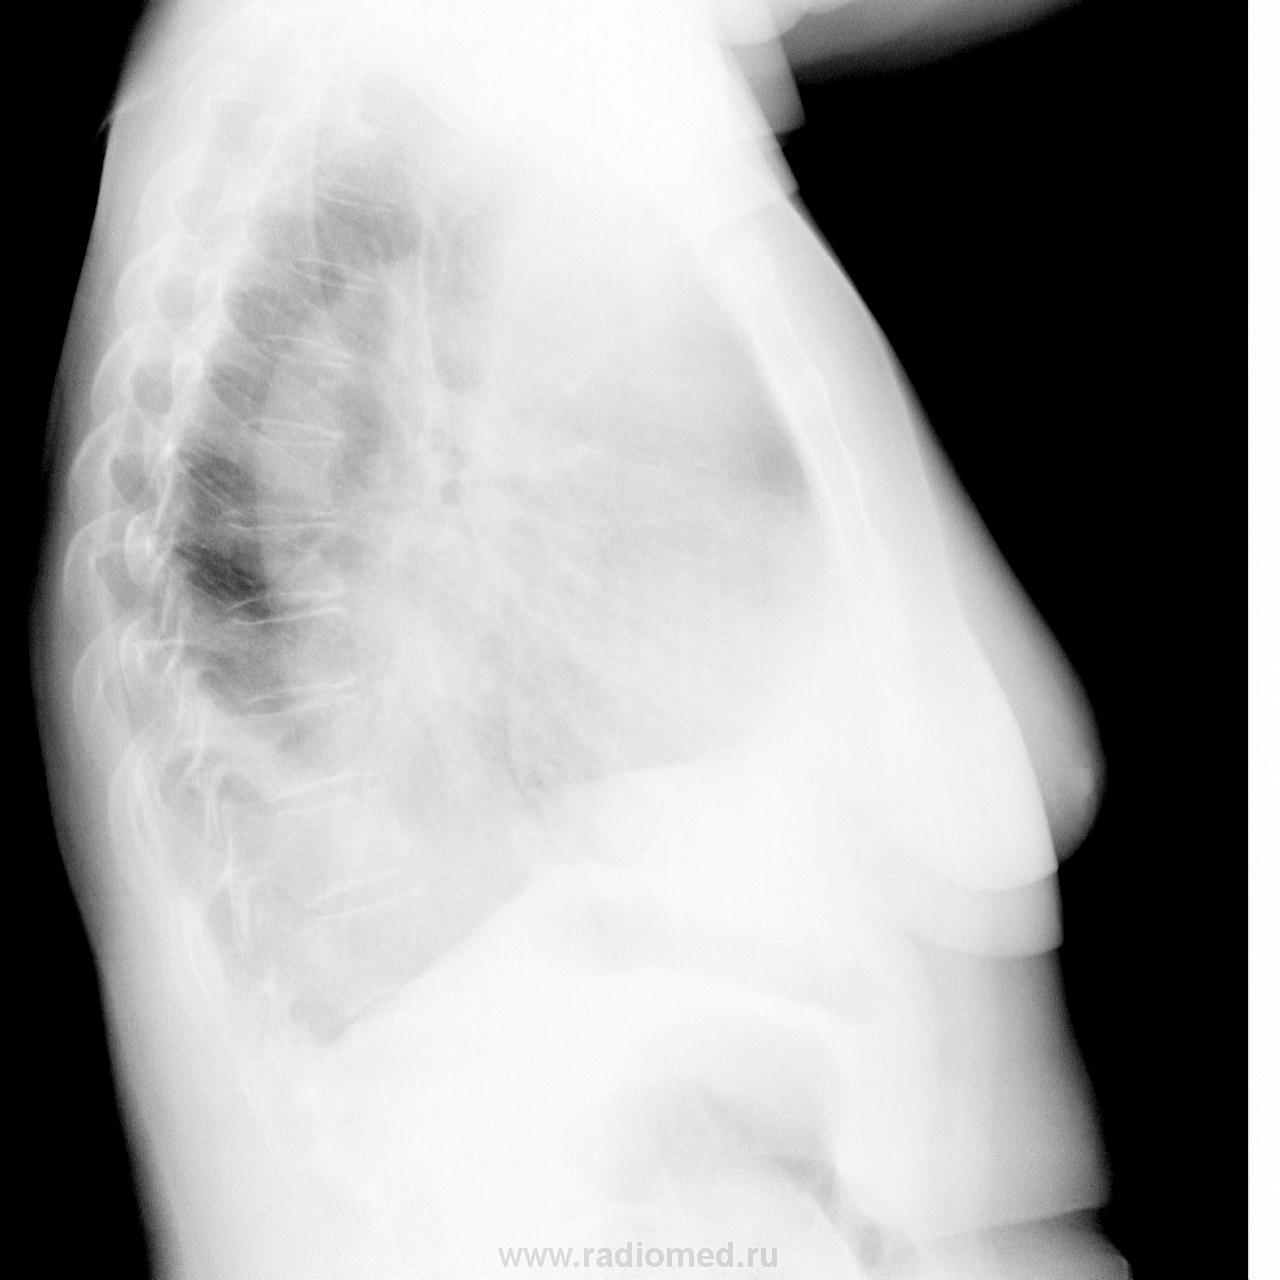

Сейчас по скорой поступила женщина, 1955 г.р. Слабость, недомогание, одышка , температура. Направили на рентгенографию грудной клетки. Выставляю флюру за сегодня и за полгода до этого . Есть или есть уменьшение обьёма справа? Да и о пропуске патологии задумался

По мне,так на первый план выходит ателектаз н/д. справа. Плеврит - "мелочь".

Есть смещение средостение справа, паракостальный осумкованный выпот справа, также дополнительнач тень, прилежащая к правым границам сердца - то ли осумкованный выпот, то ли тень коллабированной доли. Я бы не исключала ателектаз.

Пропуска не было.На "сегодняшнем" ателектаз и вероятный плеврит.

Коллеги, а ателектаз в нижней ли доле? А может всё таки в средней?

Мне больше нравится версия паракостального и парамедиастинального плеврита, пневмония в S 10 справа

Я бы написала, что определяется расширение тени средостения вправо на ---см с чётким выпуклым контуром на уровне передних отрезков____рёбер..

Ателектаз нижней доли справа. Наличие плеврита проверил бы латерограммой или УЗИ.

Версия парамедиастинального выпота и выпота в перикард.

Евгений, хороший у Вас получился вопрос, с намёком?) И никак по-другому не ответить, кроме есть! Хотя нет, ещё можно сказать, что возможен.)) Соглашусь с Вами, что объём средней доли уменьшен сейчас. Но пропуска патологии не увидал.

Поддержу коллег с версией про жидкость в полостях (парамедиастинально, паракостально...). Коллегу Дмитрия поддержу - за перикард тоже переживаю. Полисерозит какой-то у женщины. Смещения средостения нет пока. Думаю, что жидкость и туда затекла, видал такое я иногда. Сейчас дадут кортикостероидов... Надеюсь, увидим хороший контроль. Жаль, что нет позитива и муара многовато... Присматриваться приходится, а можно ведь и без прищура смотреть и даже не отходить от монитора, как предлагал нам Коллега однажды)). Хорошие снимки возможны, если работу свою хорошо сделают лаборанты... однажды.)